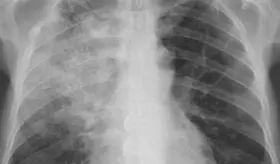

Radiólogo especialista destaca la importancia de la visión independiente del profesional en imágenes diagnósticas para detectar fibrosis pulmonar progresiva y guiar tratamientos específicos según cada patología autoinmune.

Muchas enfermedades pulmonares intersticiales pasan desapercibidas porque sus síntomas imitan a los del asma o la EPOC. Esta confusión retrasa el diagnóstico y pone en riesgo la vida del paciente.